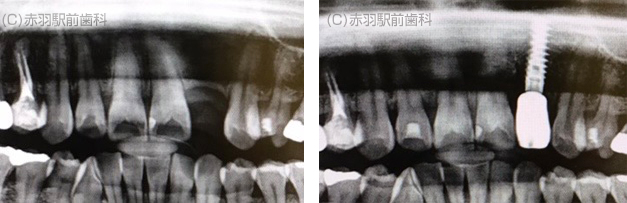

同一の患者様の口腔内写真です。

※1は他院にて数年前に埋入したインプラントです。

連結部が露出し、レントゲンで骨吸収も確認できます。

※2は当院で埋入したインプラントです。

連結部は歯肉でピッタリ適合しています。

骨吸収もないです。